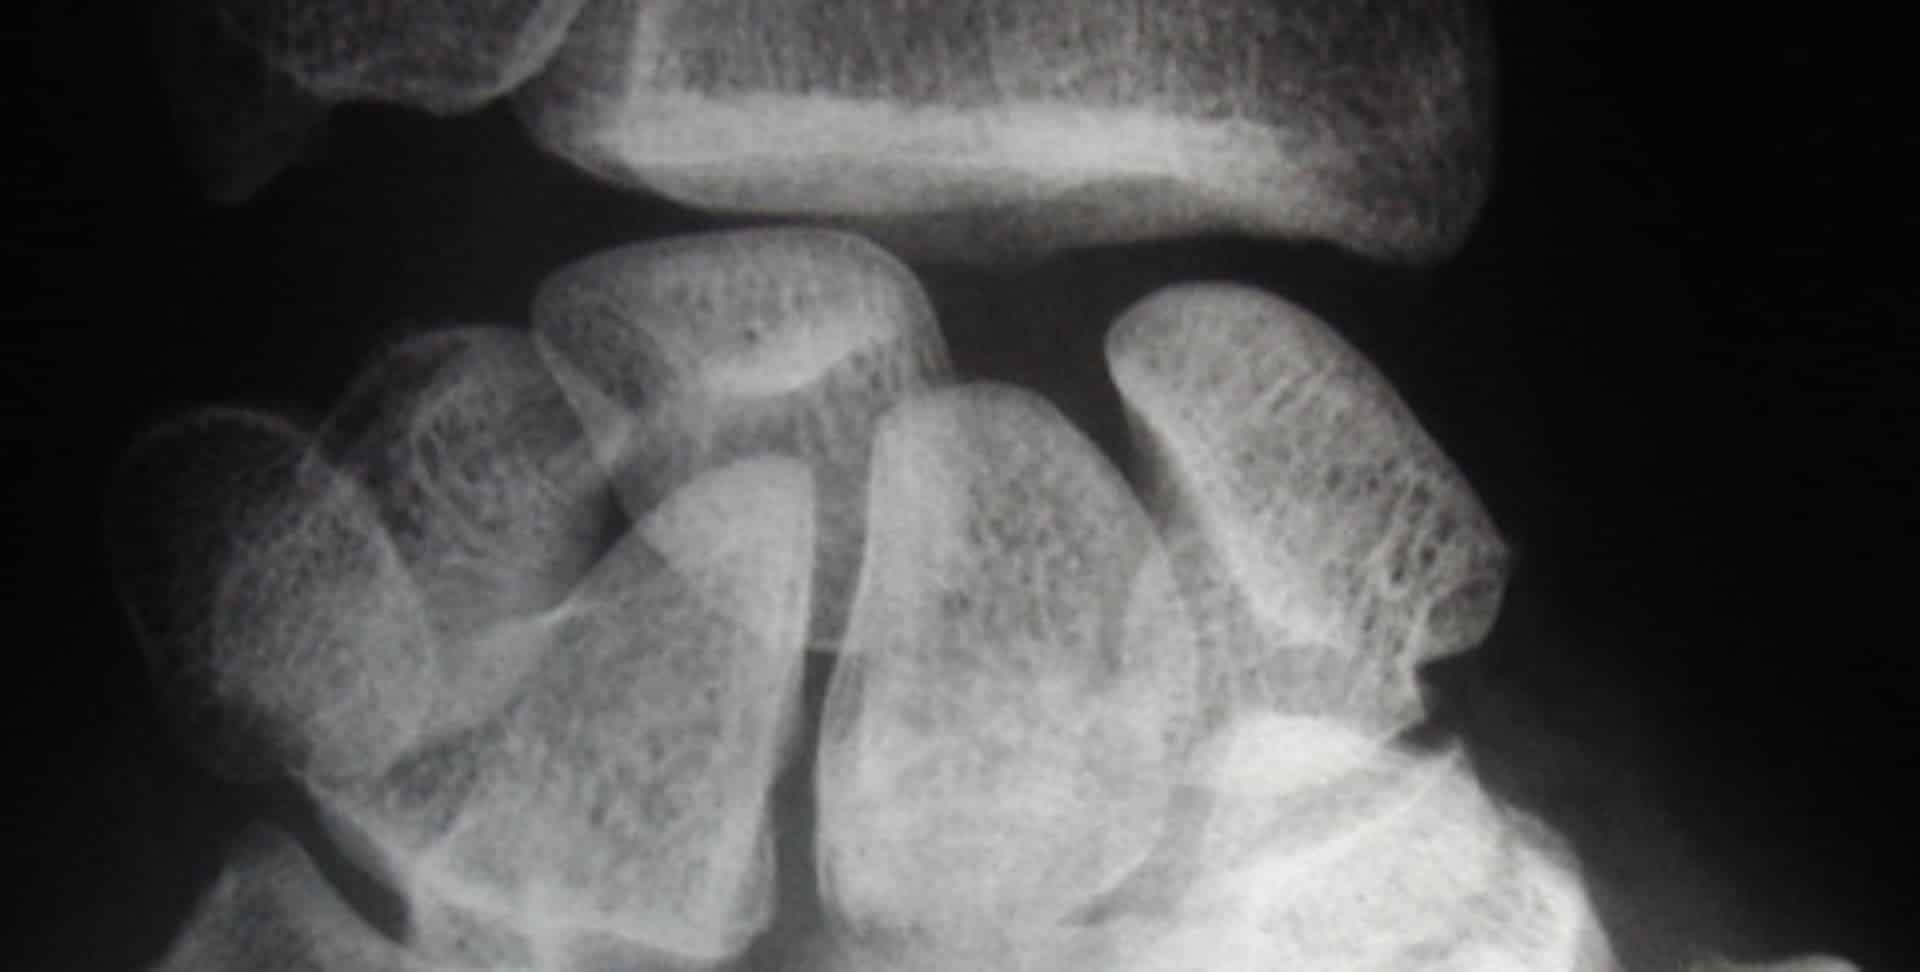

radio entorse luxation premiere rangee os carpe

Dislocation complète du carpe avec luxation de la première rangée avec rupture ligamentaire